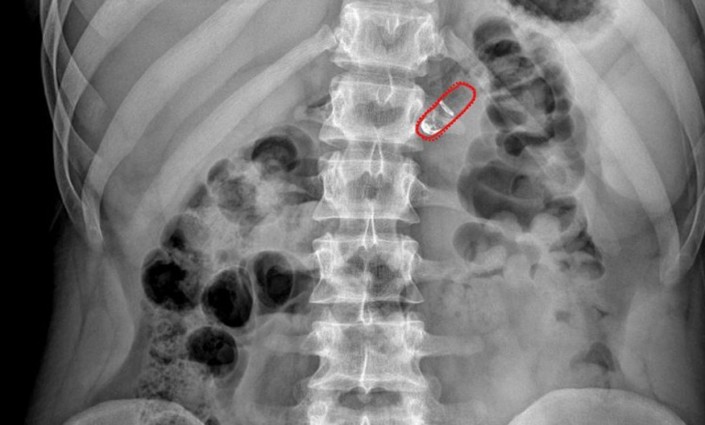

После проглатывания миниатюрного устройства в кислой среде желудка растворяются его оболочки. В результате этого два химических вещества смешиваются в специальной микроемкости и выделяется небольшое количество углекислого газа, который надувает крошечную упругую сферу, как воздушный шарик. И под ее давлением из капсулы выдвигаются иглы, которые инъецируют препарат в стенку кишечника.

Она не содержит болевых рецепторов, зато густо пронизана сетью сосудов, куда тут же попадает лекарство. Так же растворяются и остальные части капсулы вместе с иглами, сделанными из биоразлагаемого полимера, а некоторые части выходят позже с переваренной пищей. Разработчики показали, что использование RaniPill не вызывает проблем при проглатывании, прохождении по пищеварительному тракту и даже при раздувании "шарика" и срабатывании иголок.